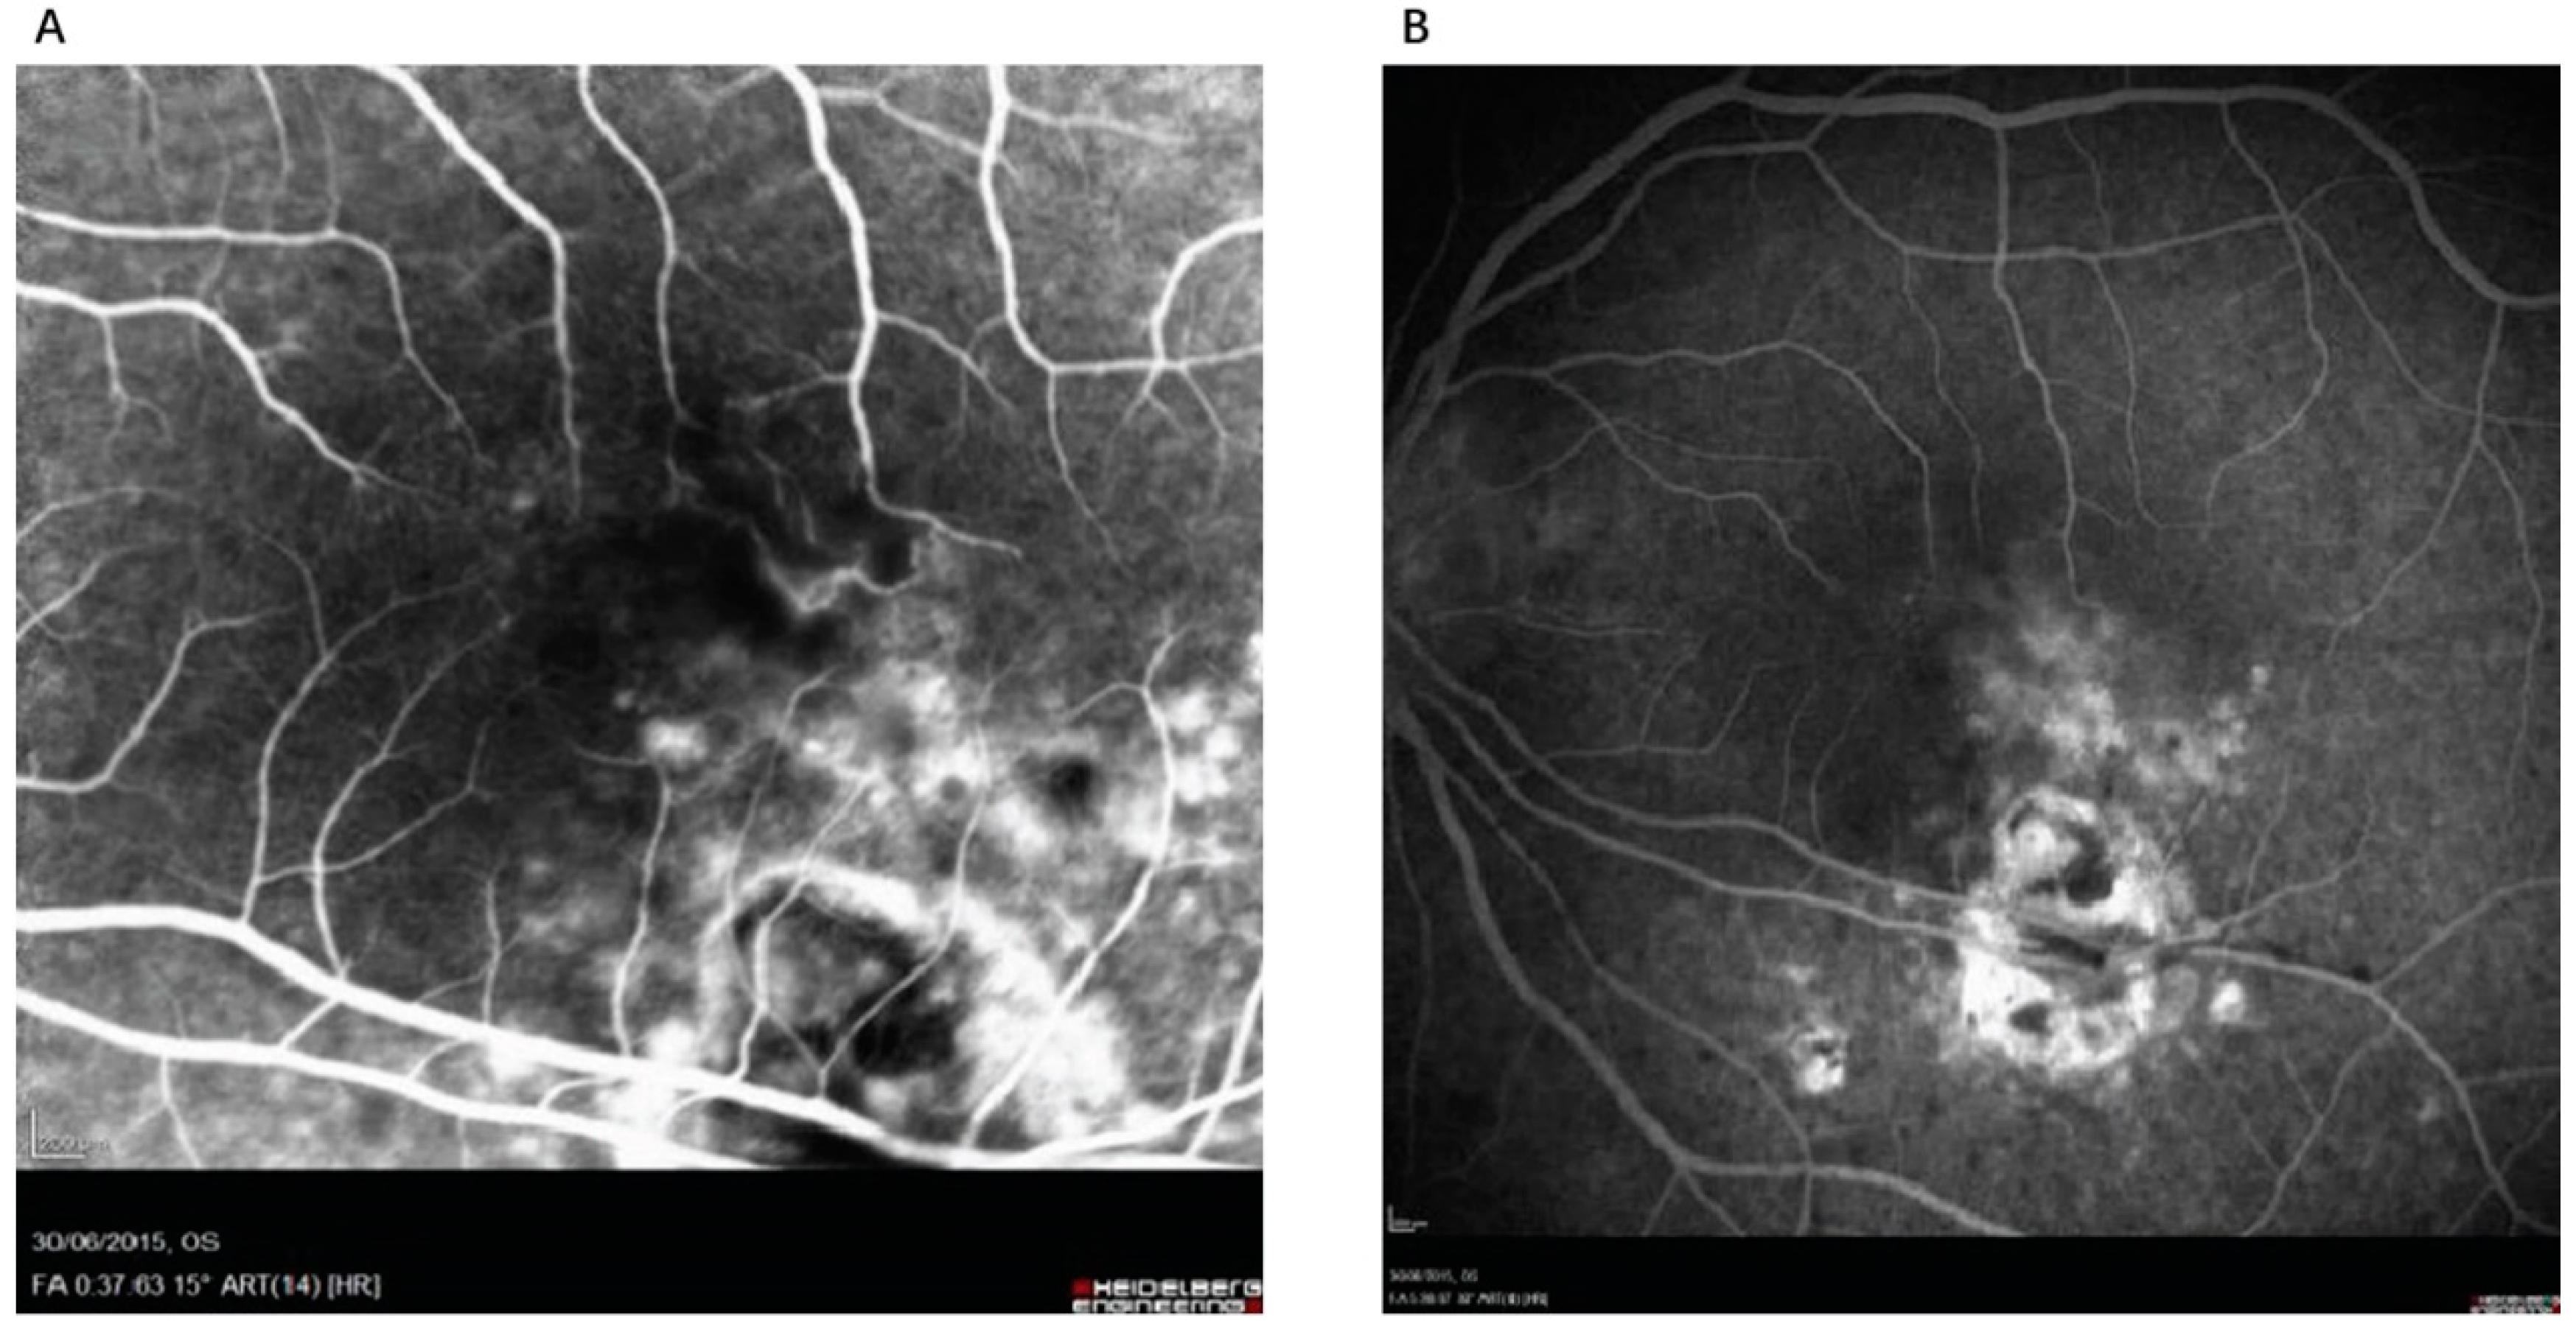

4.1. Multimodal Imaging Techniques

| Active Lesion | Gray-white necrotic foci in posterior pole with fuzzy borders; surrounding inflammation and hemorrhage | Subtle hyper/isoautofluorescence; thickening and detachment of posterior hyaloid over the lesion with irregular hyperreflective deposits | Early hypofluorescence, late progressive leakage at lesion margins; possible optic nerve head hyperfluorescence, vessel leakage, and vascular sheathing | Hypofluorescence; multiple satellite dark dots extending beyond the active retinal lesion; localized choroidal hypoperfusion | Increased intraretinal reflectivity with disorganization of neuroretinal layer boundaries corresponding to the area of retinitis; thickened and hyporeflective choroid beneath the active lesion; posterior hyaloid thickening with irregular hyperreflective deposits over the lesion | Hyporeflectivity of the lesion with diffuse choroidal dilation and many collateral vascular branches surrounding; decreased flow in outer retina and choriocapillaris | Fuzzy lesion margins, surrounding retinal edema; “headlight in the fog” appearance due to vitritis; ICGA shows multiple satellite dark dots |

| Inactive/Scar Lesion | Well-defined pigmented scar with sharp margins, often with central atrophy | Hypoautofluorescent | Early hypofluorescence due to pigment blockage or window defect, late staining at margins | Hypofluorescence; disappearance of satellite dark dots | Disorganized retinal layer reflectivity beneath a thin, hyperreflective choroid; RPE-choroid complex atrophy; persistent “hourglass configuration” with RPE changes and retina-RPE approximation | Marked reduction or absence of flow signal in all layers within the affected area | Clear boundaries, no signs of active inflammation; OCT shows tissue atrophy and “hourglass configuration” |

| Recurrent Lesion | New active lesion typically adjacent to old inactive pigmented scar (satellite lesion) | Mixture of hyper/isoautofluorescence (new lesion) and hypoautofluorescence (old scar) | Early hypofluorescence in new lesion area, late hyperfluorescence with leakage | Hypofluorescence; reappearance of satellite dark dots around new lesion | New area of retinal thickening adjacent to old atrophic area; posterior hyaloid thickening and epiretinal membrane formation | Changes in flow signal in new lesion area: increased in inner retina, decreased in outer retina and choriocapillaris | Coexistence of new active lesion and old scar; OCT shows both acute and chronic changes |